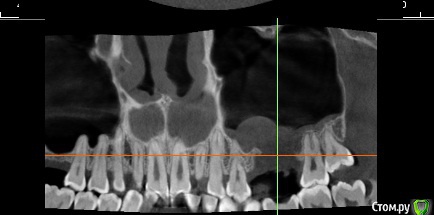

red_butler Опубликовано 30 ноября, 2016 Поделиться Опубликовано 30 ноября, 2016 Делайте Кт с захватом придаточных пазух носа. 1 Ссылка на комментарий

kyzykty1894 Опубликовано 28 декабря, 2016 Автор Поделиться Опубликовано 28 декабря, 2016 Делайте Кт с захватом придаточных пазух носа.Здравствуйте! Я сделал КТ, но никак не могу загрузить сюда Ссылка на комментарий

red_butler Опубликовано 28 декабря, 2016 Поделиться Опубликовано 28 декабря, 2016 Здравствуйте! Я сделал КТ, но никак не могу загрузить сюдаhttp://forum.stom.ru/topic/10677-kak-vylozhit-kt-na-saite/Лучше сделать нарезку, весь архив мало кто станет качать. 1 Ссылка на комментарий

kyzykty1894 Опубликовано 28 декабря, 2016 Автор Поделиться Опубликовано 28 декабря, 2016 http://forum.stom.ru/topic/10677-kak-vylozhit-kt-na-saite/Лучше сделать нарезку, весь архив мало кто станет качать.Там он как программа идет, и там можно и 3d смотреть, из за этого 50 мб весит, программа открывается на любой компьютер. Ссылка на комментарий

red_butler Опубликовано 28 декабря, 2016 Поделиться Опубликовано 28 декабря, 2016 Там он как программа идет, и там можно и 3d смотреть, из за этого 50 мб весит, программа открывается на любой компьютер. Это понятно, но многие выходят на форум с мобильных устройств и качать физически не смогут. По этому лучше выкладывать скриншоты зоны интереса. Ссылка на комментарий

kyzykty1894 Опубликовано 28 декабря, 2016 Автор Поделиться Опубликовано 28 декабря, 2016 Это понятно, но многие выходят на форум с мобильных устройств и качать физически не смогут. По этому лучше выкладывать скриншоты зоны интереса. Ссылка на комментарий